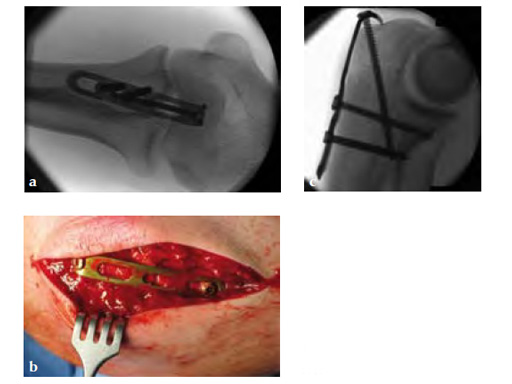

Fig 4ab Implant removal 5.5 months postoperatively.